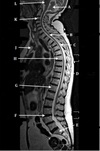

What is letter A?

SPINAL CORD

What is letter B?

LIGAMENTUM FLAVUM

What is letter C?

SPINOUS PROCESS

What is letter D?

CSF

What is letter E?

VERTEBRAL BODY

What is letter F?

STERNUM

What is letter H?

SUPRASTERNAL NOTCH

DESCENDING THORACIC AORTA

LAMINA

AZYGOS VEIN